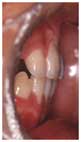

反対咬合では、下の前歯で咬みこむと、上の前歯に後ろから押される事になり、下の前歯の前面の歯肉や骨にダメージを与え、歯肉が下がったり、歯がグラグラしたりします。 | |

人の歯は、上の前歯が大きく、下の前歯が小さくできています。このため、上の前歯が下の前歯の力を受けとめるのに都合が良くなっています。 |